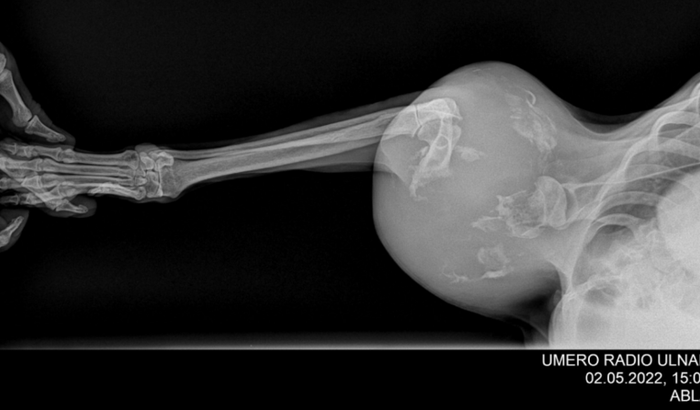

Criamos essa vaquinha para ajudar um doguinho que apelidamos de Bob. Ele foi abandonado e vagou por dias com um grande inchaço no ombro ate o levamos ao vet e tivemos uma triste notícia. Ele esta com um tumor que ja acabou com parte do seu osso e infelizmente ele precisa amputar a patinha. Nos ajude a dar a ele um final Feliz!!